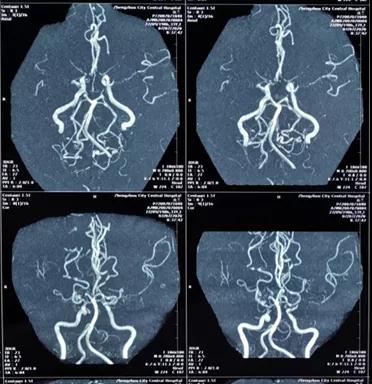

确诊为烟雾病、颅内多发动脉闭塞

完善了术前准备后,贾映海教授和四川省人民医院黄光富教授强强联手,为赵女士实施了STA-MCA(颞浅动脉 - 大脑中动脉)搭桥术,用一根比头发丝儿还细的针线在直径仅仅1mm的血管上进行搭桥。